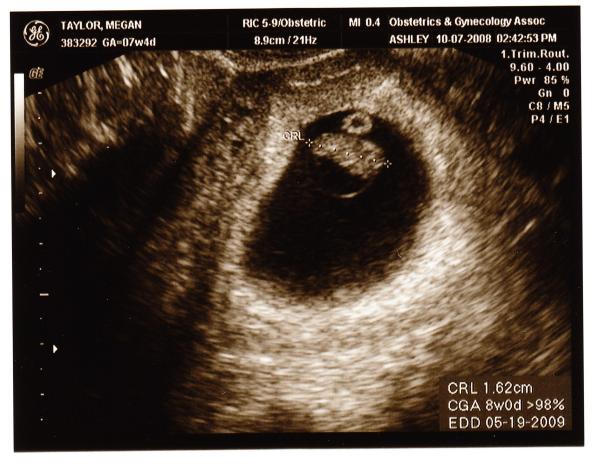

With a little fear, but with GREAT JOY Megan and I want everyone to know that we are expecting a baby! The due date is May 19 (our anniversary) and the little one is developing perfectly (or at least into a perfect peanut shape!). In the picture our baby’s heart was racing at 162 beats per minute, which is totally normal… and after the events of this year I sure both my and Meg’s hearts were beating at the same rate! Praise God!